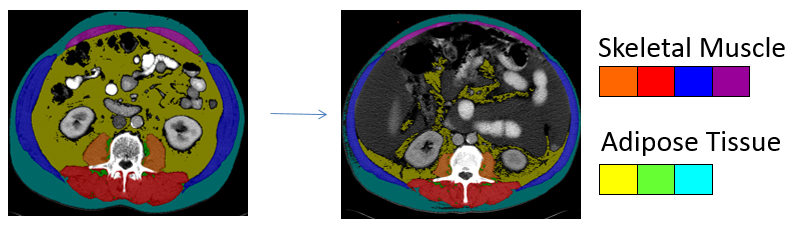

Fig. 1: To quantify different tissues for body composition analysis using computed tomography imaging, a bony landmark is used to consistently measure the same region of the body across patients. The third lumbar vertebrae is an established landmark in body composition analysis that correlates with amount of whole body muscle and fat. Each tissue attenuates radiation in a specific way which is recognised by a software program to enable skeletal muscles and different types of adipose tissues to be identified. Each tissue of interest is then colour coded. When more than one CT image exists in the patient record, tissue changes over the trajectory of the disease can be determined. This image presents two scans taken approximately six months apart at the same region within the same patient. The marked decline in muscle and adipose tissue is evident, concurrent with deposition of adipose tissue into muscle.